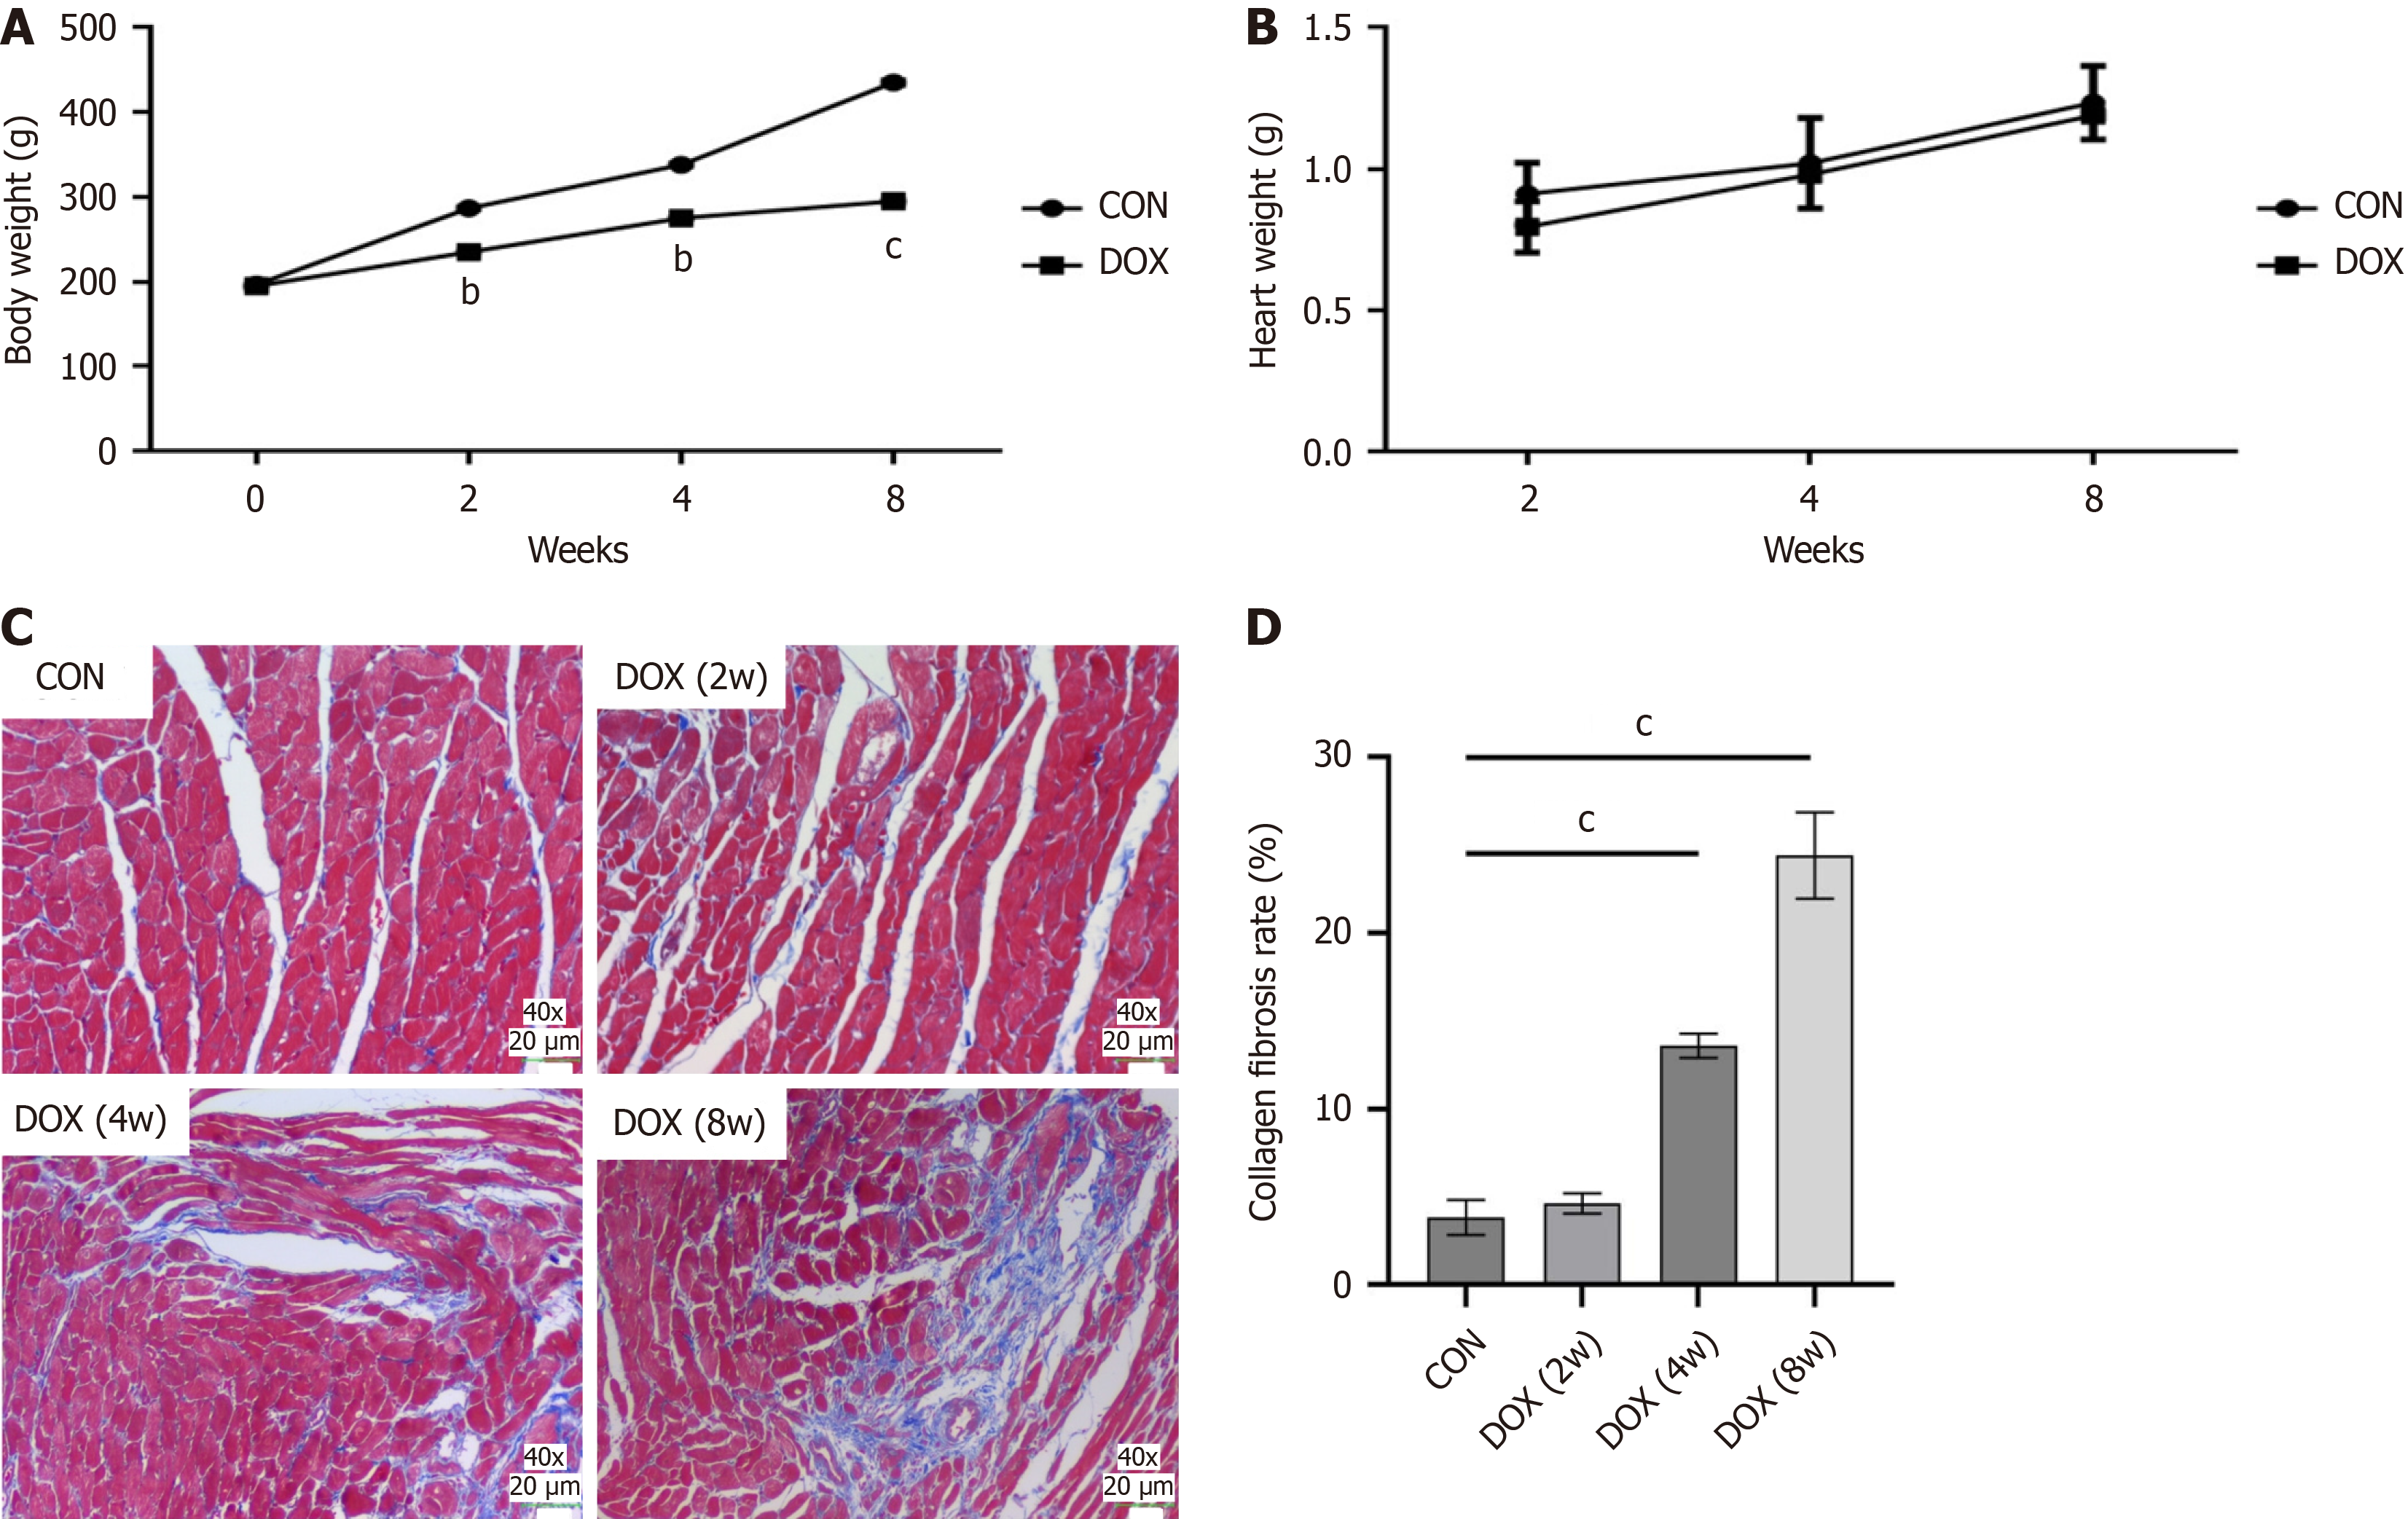

In the CON group, rats showed an increase in body weight over time, smooth and shiny fur and no mortality. However, the body weight of rats in the DOX-treated groups (2-week, 4-week, and 8-week groups) decreased significantly over time compared with the CON group (Figure 1A). The heart–body weight ratio was also significantly increased in the DOX-treated group, and this further increased with the duration of treatment (Figure 1B). These results suggest that DOX not only causes weight loss, but may also cause cardiac hypertrophy or edema.

Pathological analysis of myocardial tissue showed that cardiomyocytes in control rats were tightly arranged and orderly, with fewer intercellular collagen fibers, and no significant fibrosis was observed. However, in the DOX -treated group, cardiomyocytes were disorganized and significantly deformed, with increased cell spacing, a significant increase in intercellular blue collagen fibers, and worsening fibrosis. In particular, myocardial fibrosis was most severe in the 8-week DOX-treated group (Figure 1C). These results confirmed the direct damaging effect of DOX on myocardial tissue.